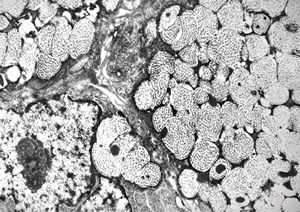

F, 24y. | molluscum contagiosum … virions

F, 24y. | molluscum contagiosum